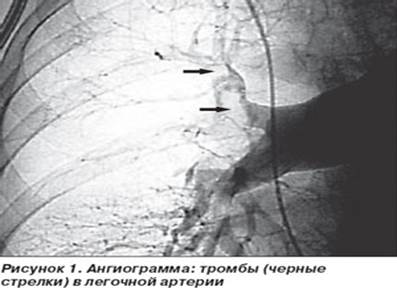

8). Ангиографическое исследование - ангиопульмонография - является золотым стандартом в диагностике ТЭЛА, подтверждающим или исключающим диагноз. Наиболее характер­ным ангиографическим признаком ТЭЛА является дефект наполнения в просвете сосуда или «ампутация», обрыв контрастирования сосуда.